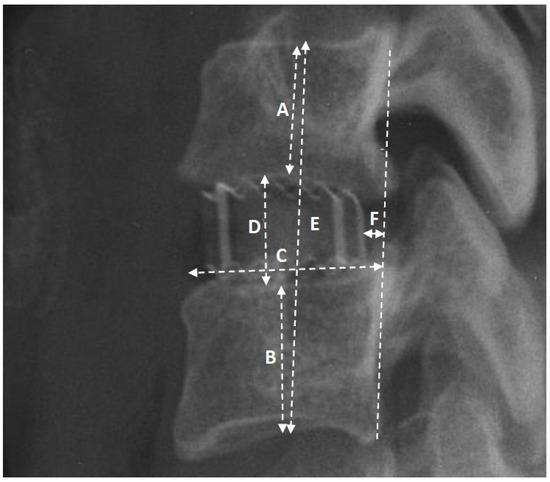

| Cage-to-endplate length ratio 1 | Mean: | 0.51 | 0.53 | 0.52 | 0.51 | 0.50 |

| Coefficient: | T = 1.79 b | H = 1.04 d | ||||

| p value | 0.0448 b | 0.5947 d | ||||

| Cage–endplate distance ratio 2 | Mean: | 0.22 | 0.17 | 0.29 | 0.18 | 0.15 |

| Coefficient: | Z = 1.53 a | H = 2.79 d | ||||

| p value | 0.1273 a | 0.2477 d | ||||

| Cage distance to endplate length ratio 3 | Mean: | 0.20 | 0.19 | 0.22 | 0.19 | 0.17 |

| Coefficient: | Z = −0.92 a | H = 2.24 d | ||||

| p value | 0.3602 a | 0.3255 d | ||||

| Cage-to-preoperative intervertebral space height ratio 4 | Mean: | 1.18 | 1.1 | 1.1 | 1.16 | 1.3 |

| Coefficient: | Z = 2.14 a | H = 4.69 d | ||||

| p value | 0.0367 a | 0.0447 d | ||||

| Cage-to-preoperative segmental height ratio 5 | Mean: | 0.18 | 0.16 | 0.16 | 0.18 | 0.2 |

| Coefficient: | −1.53 c | F = 2.54 e | ||||

| p value | 0.0322 c | 0.0389 e | ||||

| Cage to upper vertebral body height ratio 6 | Mean: | 0.41 | 0.40 | 0.41 | 0.42 | 0.40 |

| Coefficient: | T = −0.54 b | F = 0.32 e | ||||

| p value | 0.5893 b | 0.7237 e | ||||

| Cage-to-lower vertebral body height ratio 6 | Mean: | 0.40 | 0.40 | 0.40 | 0.41 | 0.37 |

| Coefficient: | Z = 0.27 | F = 2.27 e | ||||

| p value | 0.7855 a | 0.1100 e | ||||